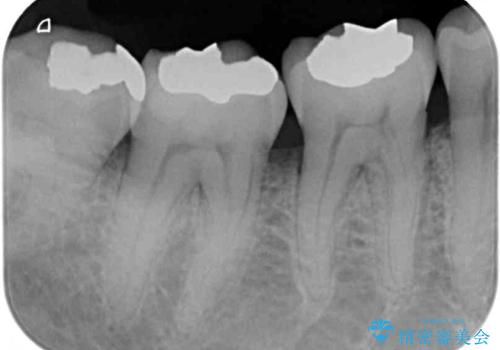

- 銀歯やインレーが外れたまま放置された奥歯の治療を希望して来院された患者様です。

咬合力が著しく強いため、欠損の多い歯はフルジルコニアクラウンへ、その他の虫歯はゴールドインレー(PGAインレー)にて修復することとしました。